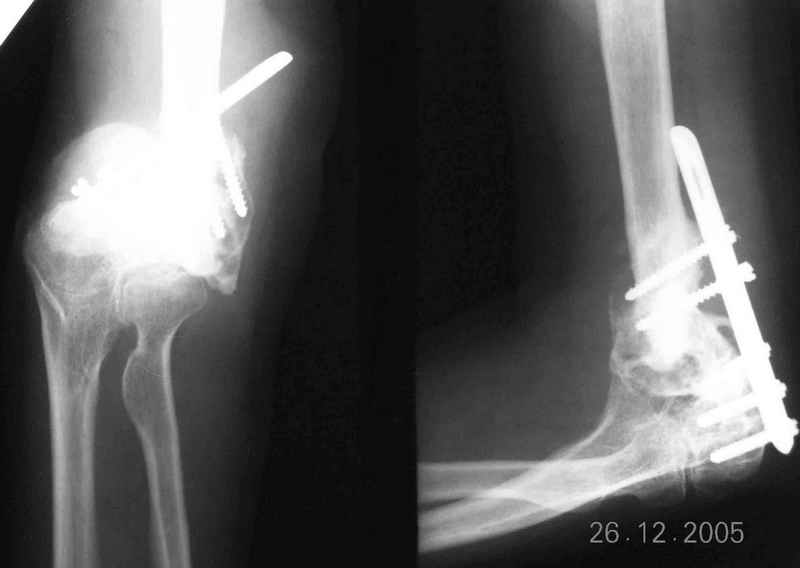

Re: Болтающийся ложный сустав дистального плеча

Уважаемый Ильдар, в ноябре 2005 г. мы оперировали практически полностью идентичную ситуацию у больного с гемофилией, поставили модифицированный

эндопротез локтевого сустава типа Сиваша с хорошим результатом. На заводе-производителе (в нашем случае - завод ЦИТО, но есть еще ООО

Эндосервис т/ф (095) 221-06-18, 500-41-30, 513-54-32 ) можно заказать протез этого типа по индивидуальным размерам для восполнения дефицита длины плечевой кости. Сейчас есть и более дорогие коммерческие эндопротезы фирмы Stryker. Наиболее активно оперируют локоть в ЦИТО, у нас тоже есть

собственный небольшой опыт эндопротезирования локтевого сустава.